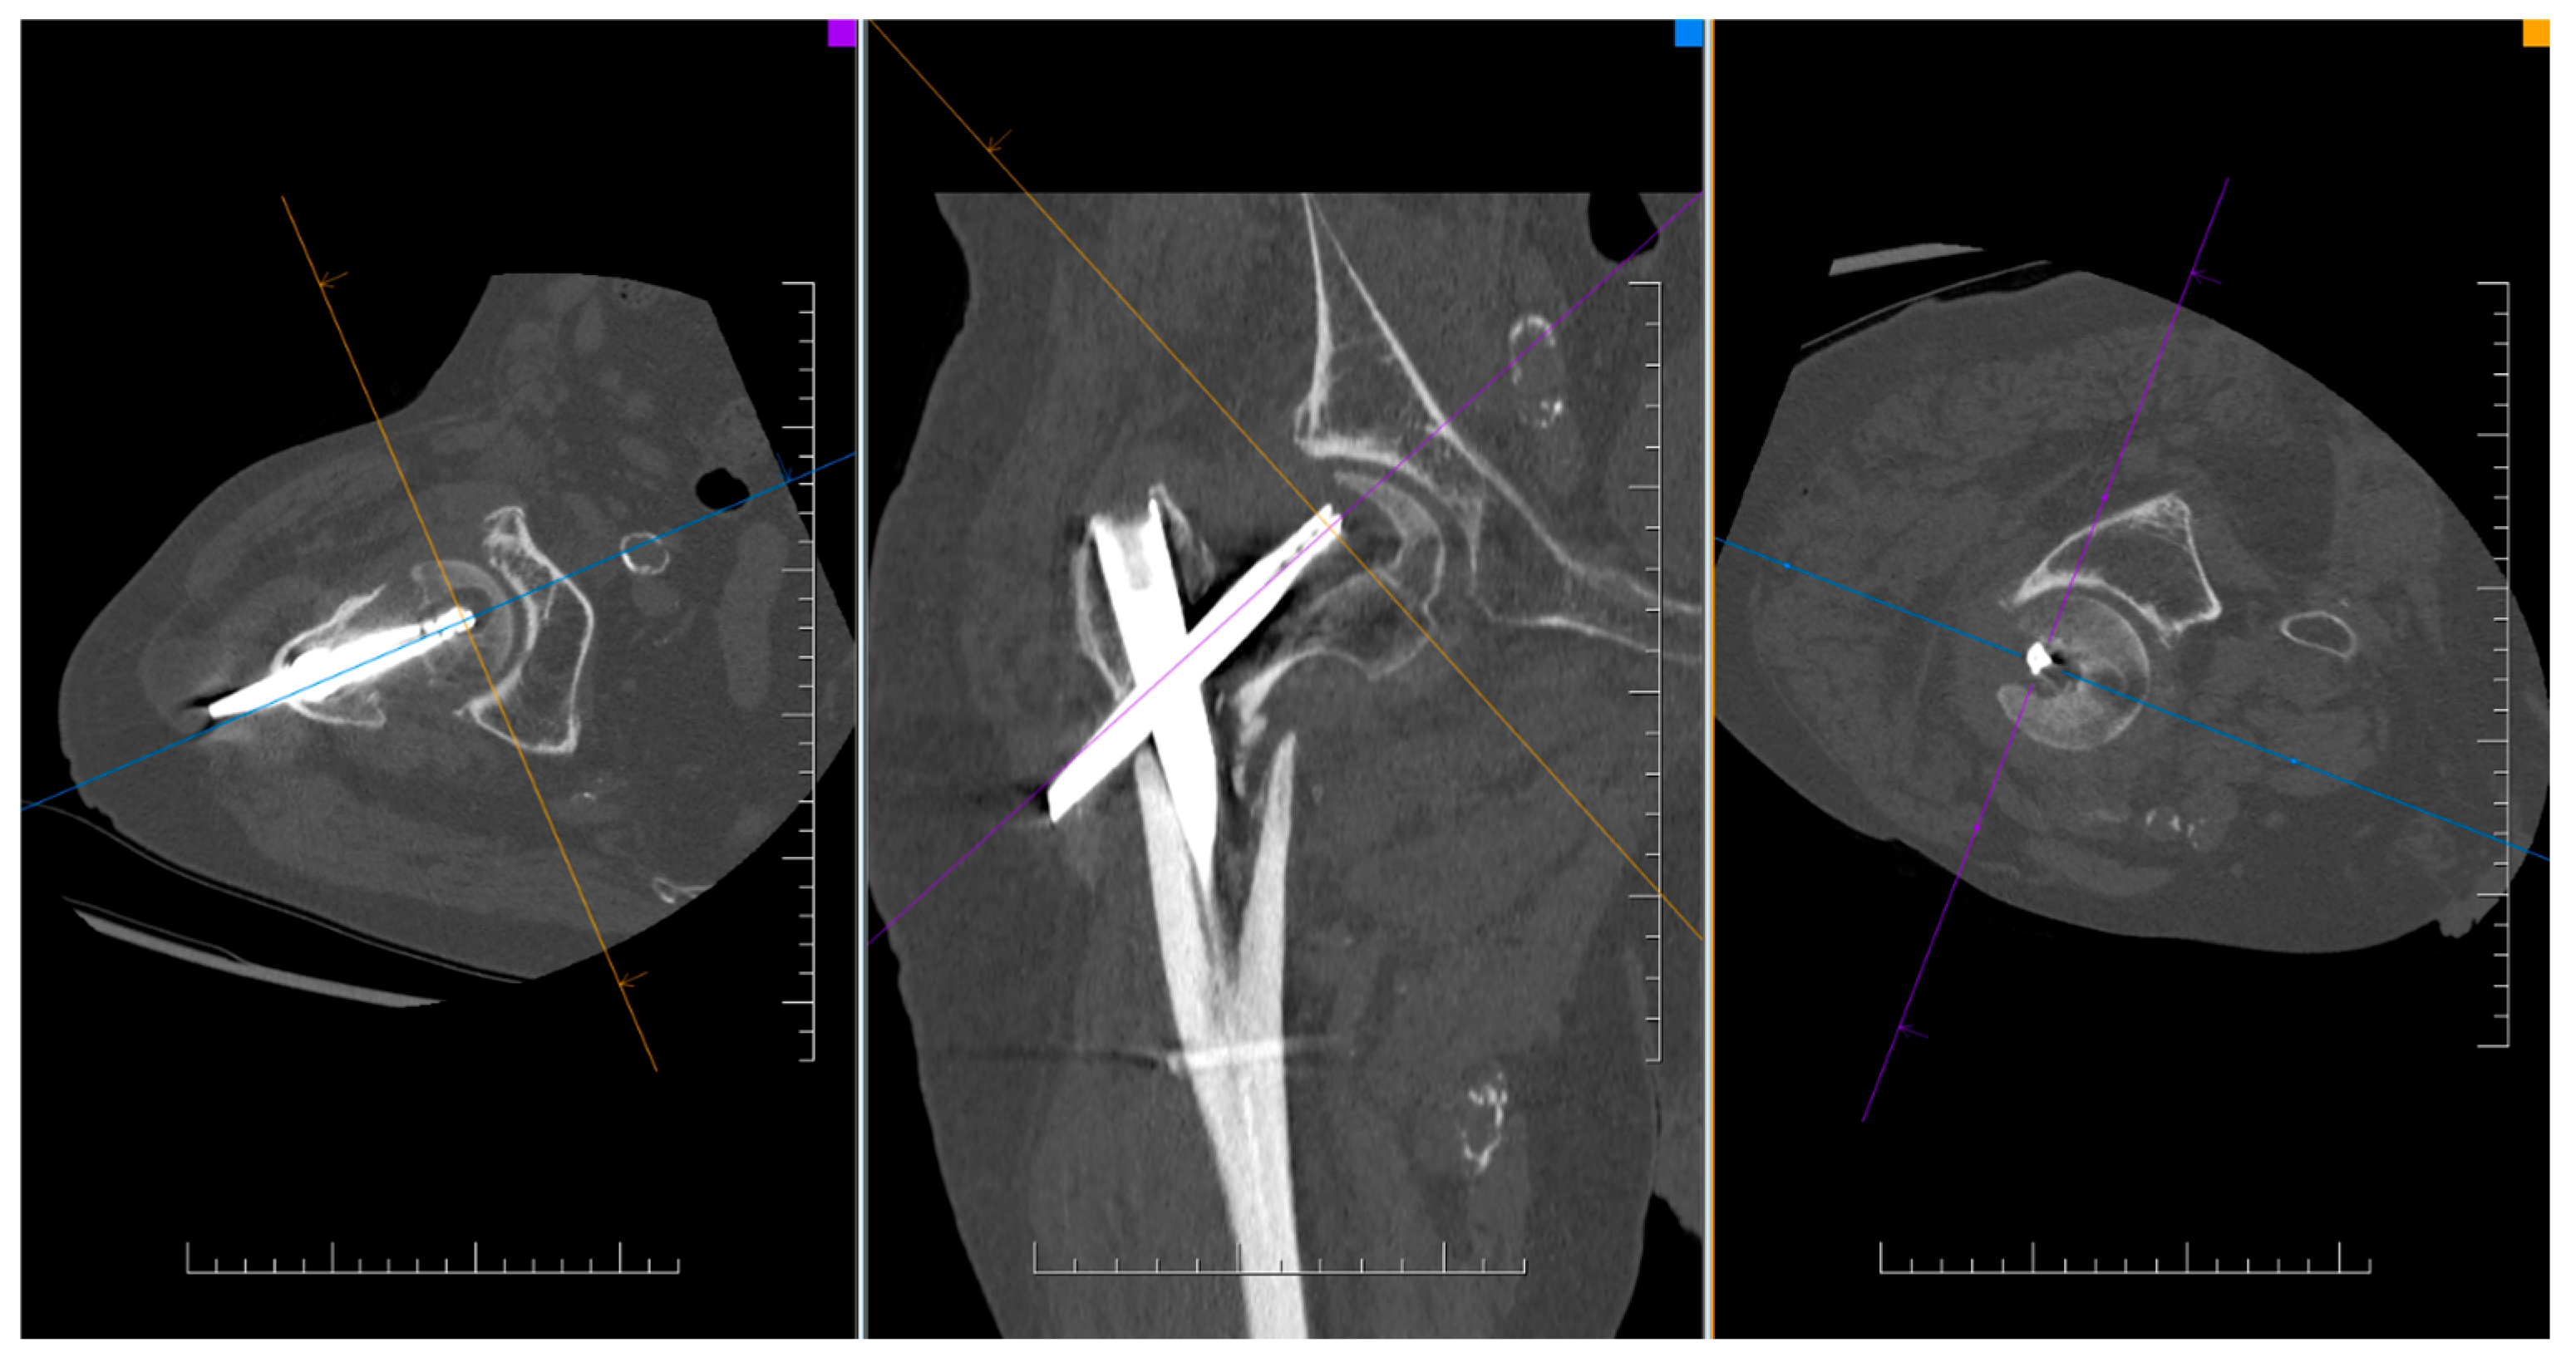

Figure 3.

CT finding of osteosynthesis failure using TFNA without cement augmentation of the blade and with cut-out.

By evaluating the X-ray parameters, eight patients in the cohort in whom postoperative varus deformities of the femoral neck were greater than 10° were founded. Four patients did not have cement augmentation and four had cement augmentation of the nail. In three cases, the blade cut-out and, thus, failure of osteosynthesis was identified. In two women and one man with blade cut-out, a TFN-A implant without cement augmentation was implanted (Figure 3, Figure 4 and Figure 5). In these three cases, the medial cortical line and anterior cortical line were repositioned within 3 mm of dislocation at the anatomical interface. The blade cut-out in the group with cement augmentation was not observed.